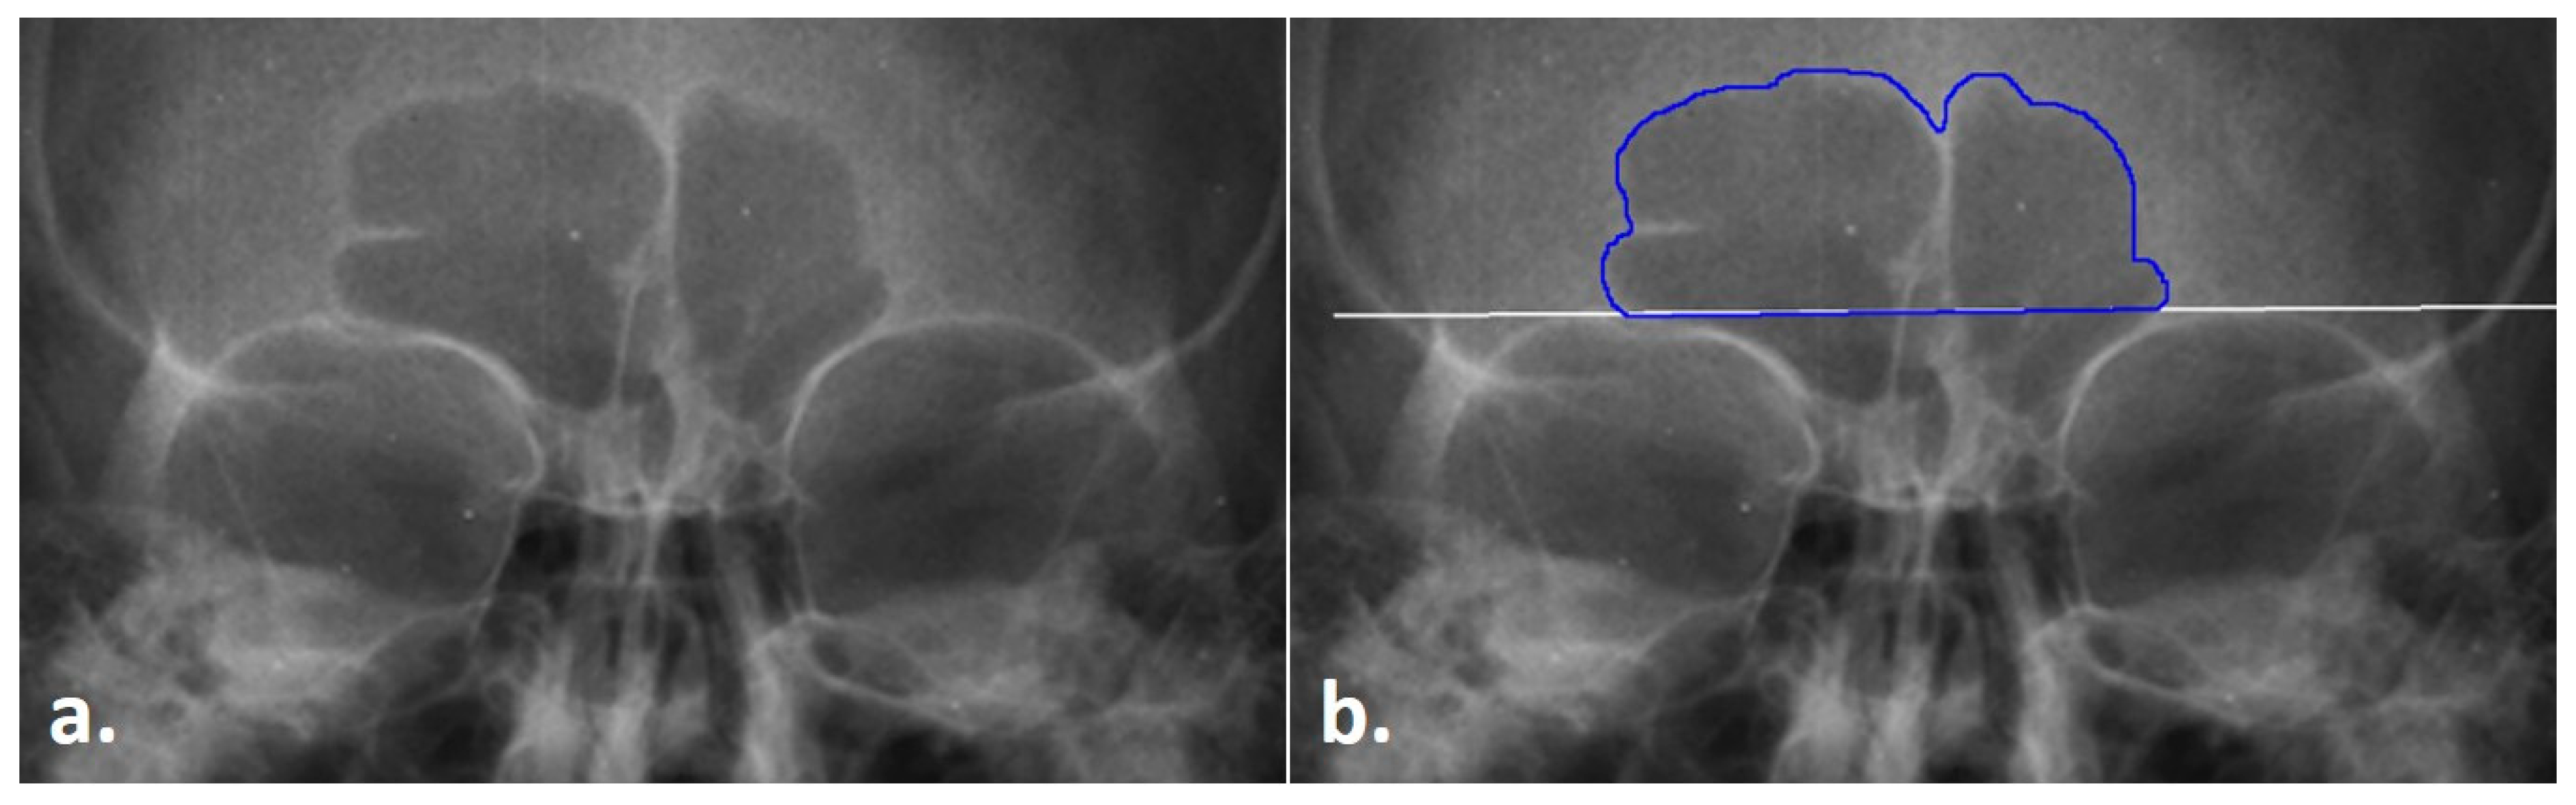

Prior to collecting data in the three modes (see below), the first step of the TDM is to obtain the frontal sinus outline. In this step, .png radiographic images downloaded from the Legacy Collection were opened in ImageJ. The images were increased to 3000 pixels. Following Christensen [14,17] and Cox et al. [16], the inferior boundary of the frontal sinus was demarcated at the supraorbital line using the line tool in ImageJ. From this line, the lateral and superior edges of the sinus were traced from the left to the right side of the image (clockwise fashion) using the Freehand tool in ImageJ; note that only the outer contours were traced, and individual septa were not followed inferiorly into the sinus, following Christensen [14,17] (see Figure 1). To avoid potential inter-reliability errors in the sinus outlines not directly related to the TDM, the outlines were only traced by a single researcher. Each outlined image was saved as a .tiff file for future processing, as detailed below.

Figure 1. Radiograph of the frontal sinus; (a) untreated radiograph, (b) frontal sinus with the outline (blue) and supraorbital line (white).